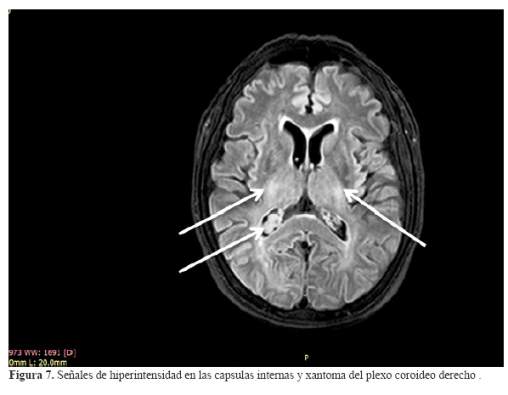

La exploración neurológica mostró marcadas alteraciones en la esfera emocional, adoptando un comportamiento infantil, con variaciones en el ánimo y en el interés para realizar el test, minicognitivo de Folstein así como, a los resultados en cada uno de los ítems conocidos, en los que frente a las fallas, no le suscitaban incomodidad o ansiedad . La puntuación de la prueba neuropsicológica fue de 8 puntos con fallas en la orientación temporal , mencionando sólo el día de la semana, estaba desorientada en lugar y tuvo groseras fallas en la memoria inmediata retuvo dos de tres palabras y al minuto las olvidó completamente; nivel de atención igualmente afectada finalmente en la copia de los pentágonos entrelazados graficó un pentágono adjunto a un cuadrado. Presentó anhedonia frente a los resultados. No tuvo afasia, apraxia ni agnosia. Presentó incoordinación y adiadocinesia asimétrica, marcha atáxica zigzageante. Moderada debilidad en la fuerza muscular contra resistencia que se acompañó de reflejos vivos y ausencia de los signos de Babinski y el de Hoffmann. La exploración de la sensibilidad supeficial y profundas normales. Concluyéndose clínicamente el compromiso del vermis y los hemisferios cerebelosos, puso en evidencia el estado demencial al obtener una puntuación de ocho en el test de Folstein, no disartria, incoordinación axial y de los miembros y la marcha zigzageante, Cuadriparesia moderada en los miembros, sin signos patológicos, reflejos tendinosos presentes. Con estos resultados se produjo la exploración mediante resonancia magnética del cerebro (RM) contrastada , incidiendo en T1,T2 y el FLAIR, que mostró: atrofias comprometiendo las regiones fronto – témporo – parietales, el cuerpo calloso y el cerebelo ( figura 6 ). En la incidencia con el FLAIR se observó: hiperintensidad en las cápsulas internas, pedúnculos cerebrales y en las fibras transversas de la protuberancia. En forma accidental el hallazgo de un considerable quiste aracnoideo temporal izquierdo que no tuvo mayor implicancia clínica en el estado de la paciente (figura 6, figura 7, figura 8 y figura 9)

Los xantomas tendinosos aquilianos, biopsiados mostraron la naturaleza de la enfermedad, al igual que la presencia del arco senil tempranamente aparecidos, antes de los 30 años, las cataratas, la presencia de xantoma en el cuerno ventricular derecho por la especialidad y la osteoporosis estarían indicando un estado avanzado de la enfermedad por XCT. El estudio con resonancia magnética del cerebro (RM), puso en evidencia los cambios morfológicos del tejido cerebral, asi como , la penetrancia del colagenol en estructuras específicas empleando la incidencia del FLAIR.

El estudio mediante el empleo de la resonancia magnética cerebral fue decisivo para explicar las alteraciones anteriormente precisadas e interpretar la etiología al visualizarse la presencia del colastenol en diferentes localizaciones del tronco encefálico, así como, las regiones atróficas de los hemisferios cerebrales comprometidas y que explicaban la demencia como la ataxia.